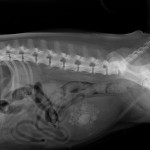

caillou a la radio

Radiographie de profil d’un chien ayant avalé un caillou